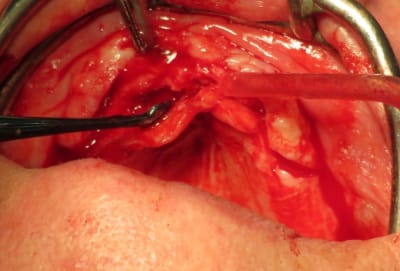

voici ce qui a été fait par un chirurgien maxillo en AG qui avait à son actif une vingtaine d'implants posés, la S.I.A.O (17), pose des guides à appuis osseux (18, 19), résultat fin de chirurgie (20).